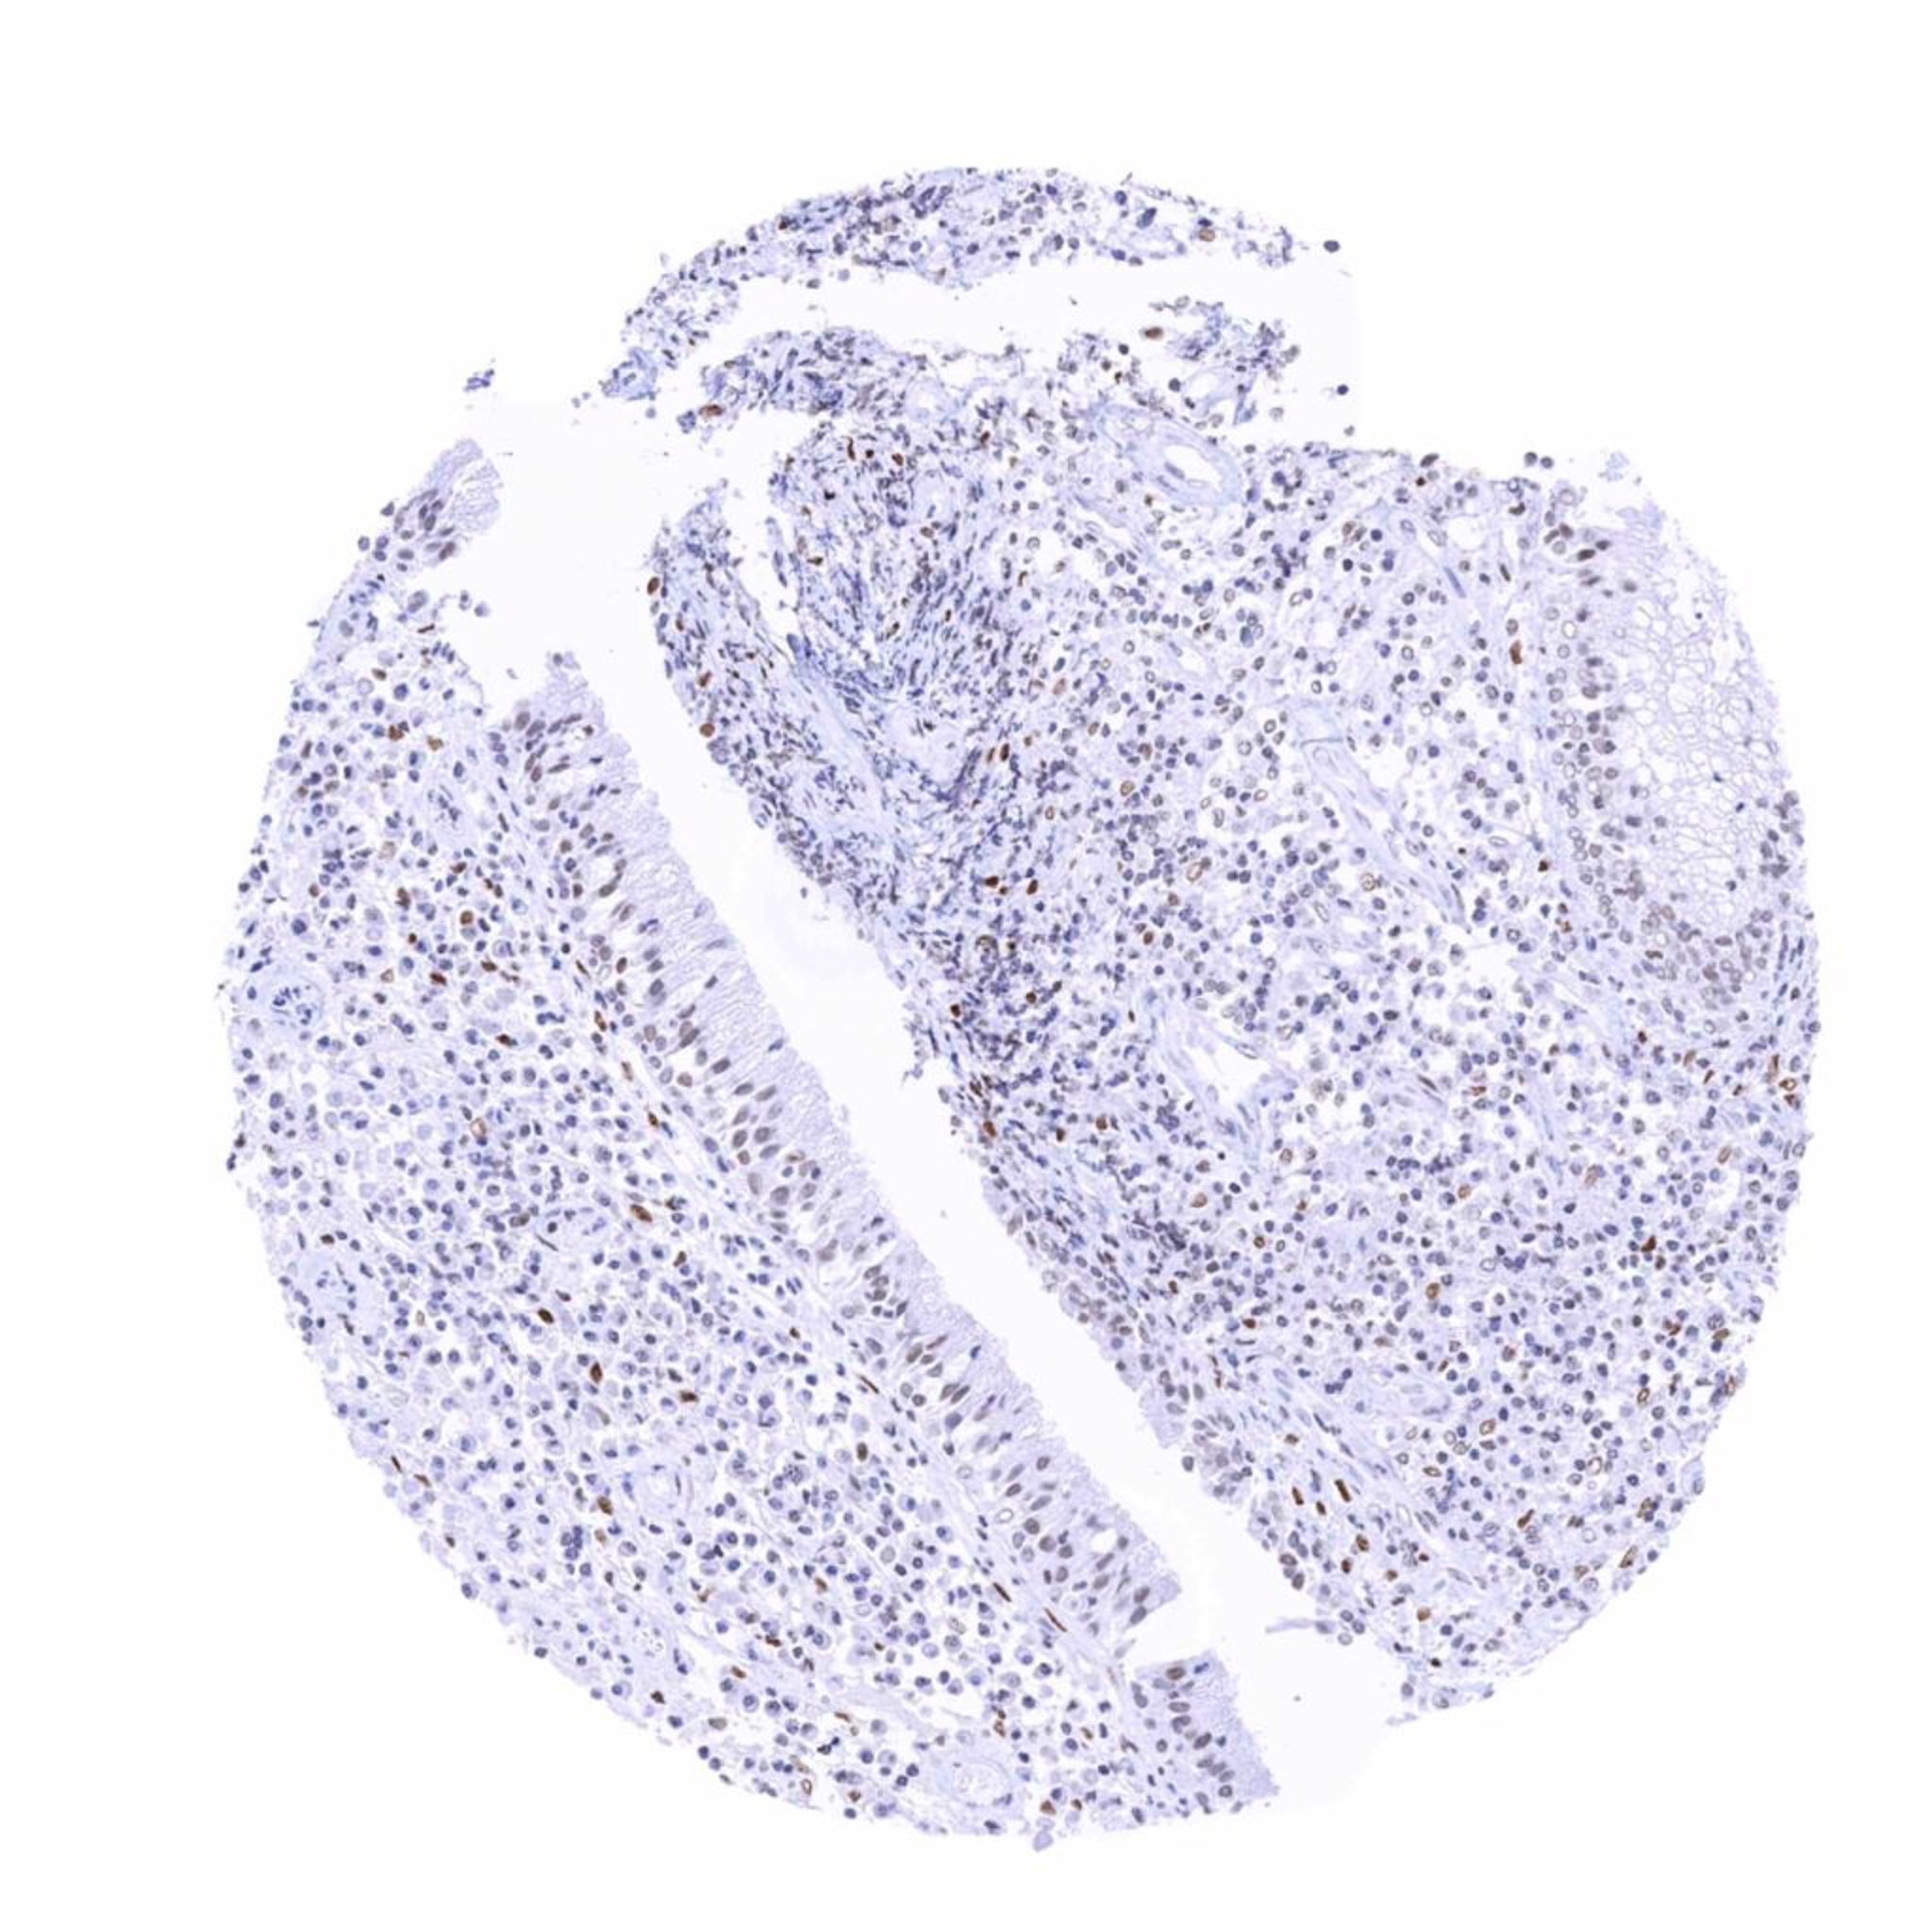

Prostate – Variable (faint to moderate) nuclear TRPS1 staining in acinar cells. Probably depending on functional status. Weak to moderate staining of (muscular) stroma cells